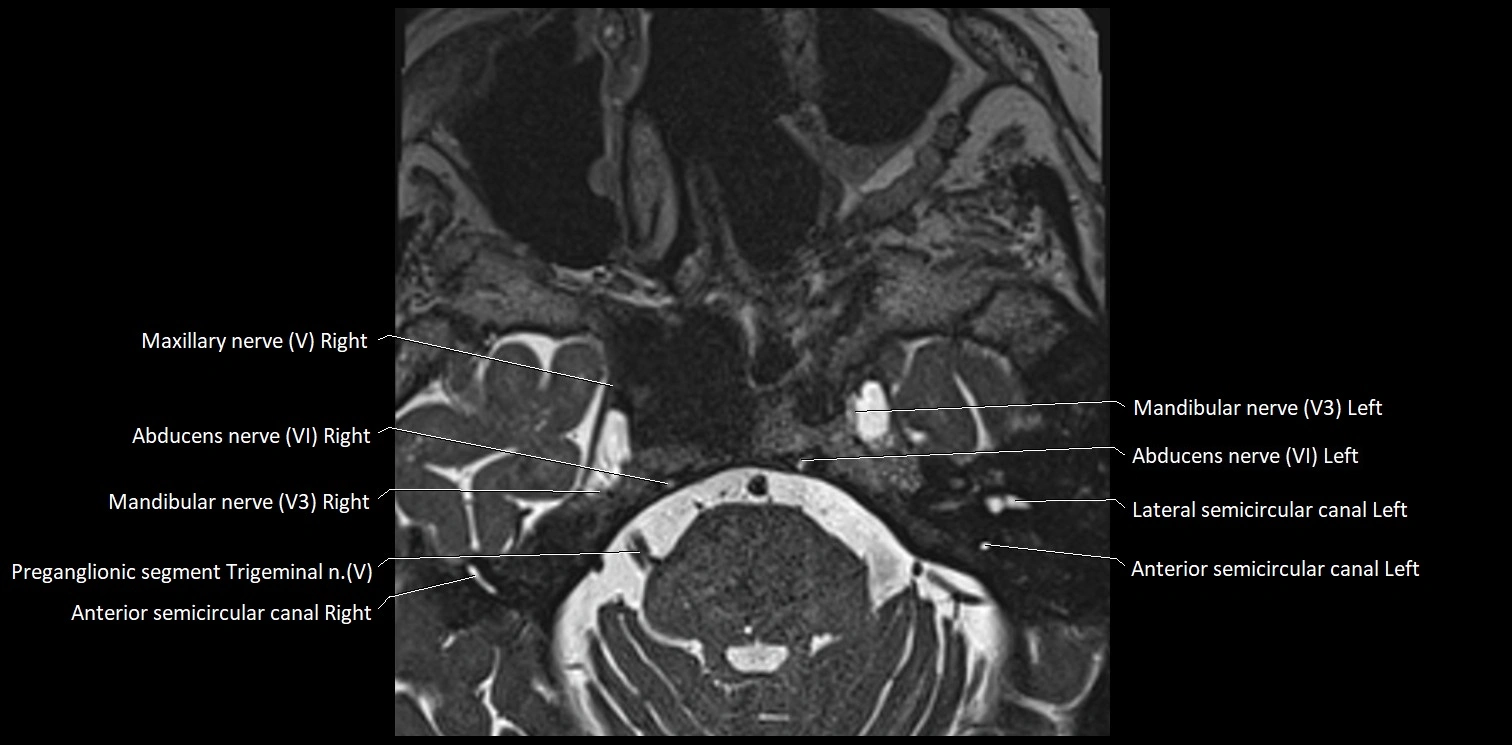

MRI Appearance

• The abducens nerve is a small, thin, linear structure

• Best visualized on high-resolution T2-weighted 3D MRI sequences (e.g., FIESTA or CISS)

• Seen as a hypointense (dark) line running from the brainstem at the pontomedullary junction, traversing the prepontine cistern, and entering Dorello’s canal under the petrosphenoidal ligament, then into the cavernous sinus, and finally the orbit

• May be challenging to visualize in standard MRI due to its small size

• Pathology may be inferred by absence, displacement, or enhancement of the nerve

MRI images

image